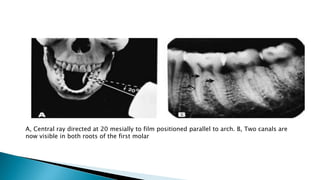

A, Central ray directed at 20 mesially to film positioned parallel to arch. B, Two canals are

now visible in both roots of the first molar

A, Central raydirected at 20 mesially to film positioned parallel to arch. B, Two canals are now visible in both roots of the first molar